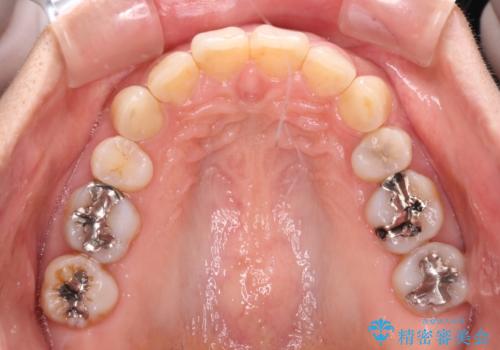

- 以前行った抜歯矯正が後戻りし、開いてしまったスペースが気になるとのことで来院された患者様です。

インビザラインを用いて開いてしまったスペースと前歯のデコボコを改善することとしました。

矯正治療後には気になっていた銀歯をセラミッククラウンやセラミックインレーにて治療することとしました。

上顎前歯を左右対称となるように歯列を整えたいとのことでしたが、すり減って形態が大きく異なっていたため、できる範囲での仕上がりとなりました。